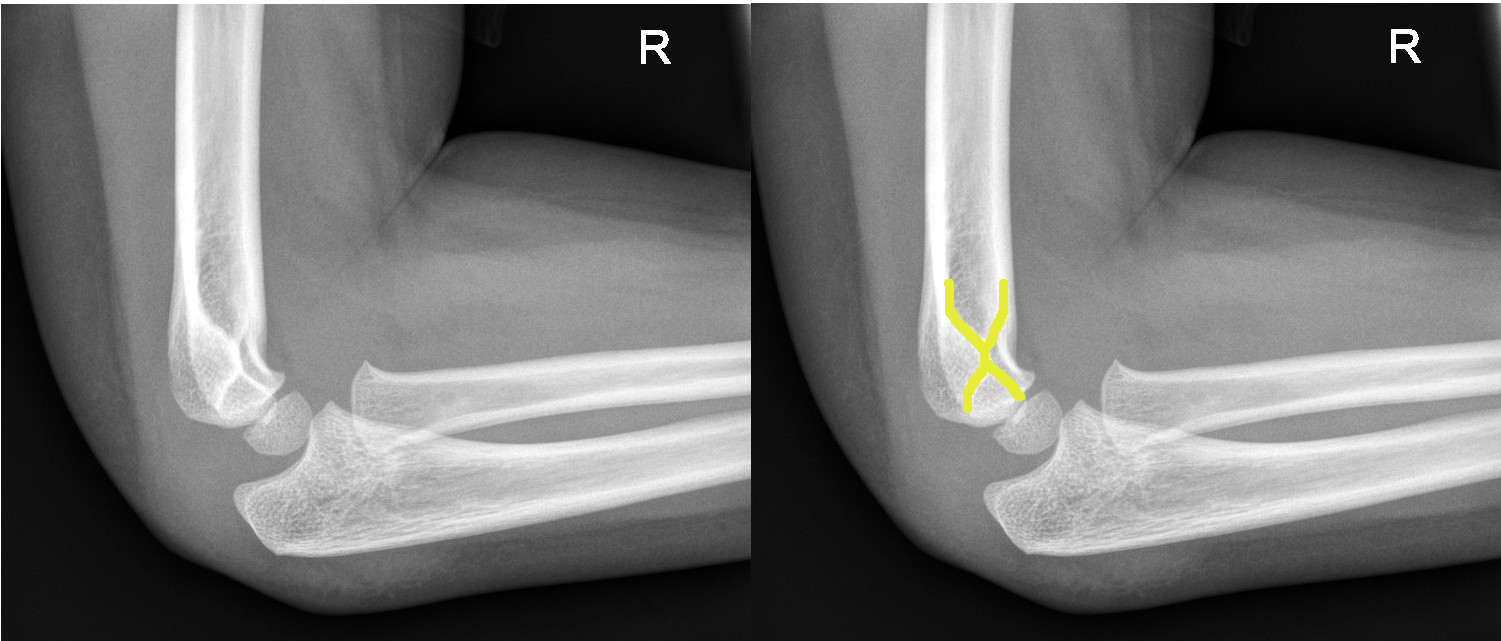

Lateral condyle fractures

- All lateral condyle fractures should be discussed with the Orthopaedic team for further management. They are generally unstable and prone to displacement and often require operative fixation.

Lateral condyle fracture